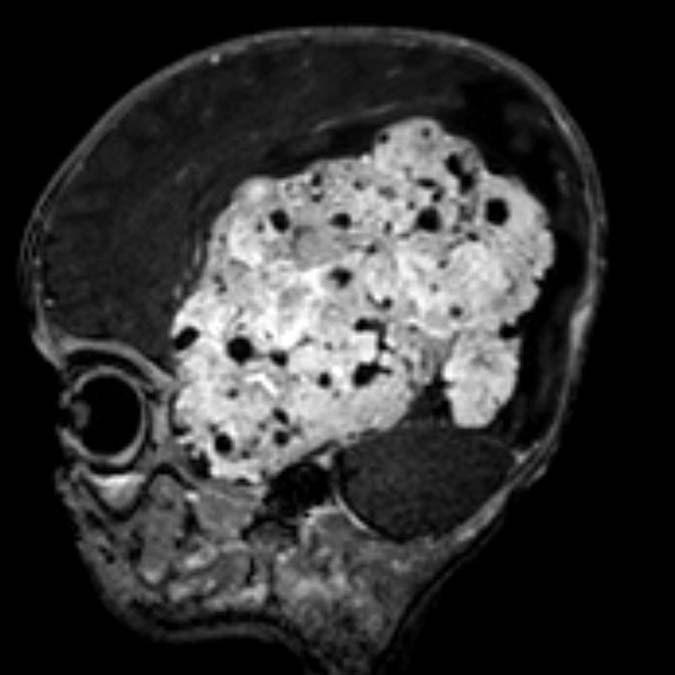

Şanlıurfa’da 1,5 yıllık evli Saniye ve Yunus Kılıç, 3 aylık bebekleri Mehmet Asaf Kılıç’ın kafasının sol tarafında oluşan şişliği fark edince Şanlıurfa Eğitim ve Araştırma Hastanesi’ne başvurdu. Beyninde kitle olduğu belirlenen Asaf bebek, Ankara Sağlık Bilimleri Üniversitesi Gülhane Eğitim ve Araştırma Hastanesi’ne sevk edildi. Asaf’ın çekilen MR’ında beynin sol tarafının tamamen tümör ile kaplı olduğu tespit edildi. Asaf bebeğin ameliyat edilmesi kararlaştırıldı ve 9 saat süren operasyonla beynindeki tümör temizlendi. Asaf bebek, tedavi sürecinin ardından sağlığına kavuştu.

Mehmet Asaf’ın doktoru Beyin ve Sinir Cerrahisi Uzmanı Doç. Dr. Cahit Kural, Asaf’ı ilk gördüklerinde yolunda gitmeyen bir şeyler olduğunu hissetiklerini belirterek, “Acil olarak MR çektirdik. Beyin MR’ında beynin sol tarafını tamamen dolduran, sağ tarafına bası yapan devasa bir kitle vardı. Zaman kaybetmeden hemen ameliyata aldık. Ameliyatta tümörün tamamını çıkardık. Bu büyüklükte tümörler çok nadir görülür. Beynin yarısını dolduran bir tümördü. Hastamız çok küçük, tümör çok büyük, riskli bir ameliyattı. 8-9 saat süren bir ameliyatın ardından iyileşti, sağlıklı şekilde evine gönderiyoruz” dedi.

Çıkarılan örnekleri ileri inceleme için patoloji bölümüne gönderdiklerini belirten Kural, “‘Atipik koroid pleksus papillomu’ tanısı geldi. Bu çok nadir görülen bir tümör. Beyni bu kadar dolduran tümör görmek, çoğu zaman mümkün değil. Tümörün hepsini çıkardığımız için kemoterapi düşünmüyoruz” diye konuştu.